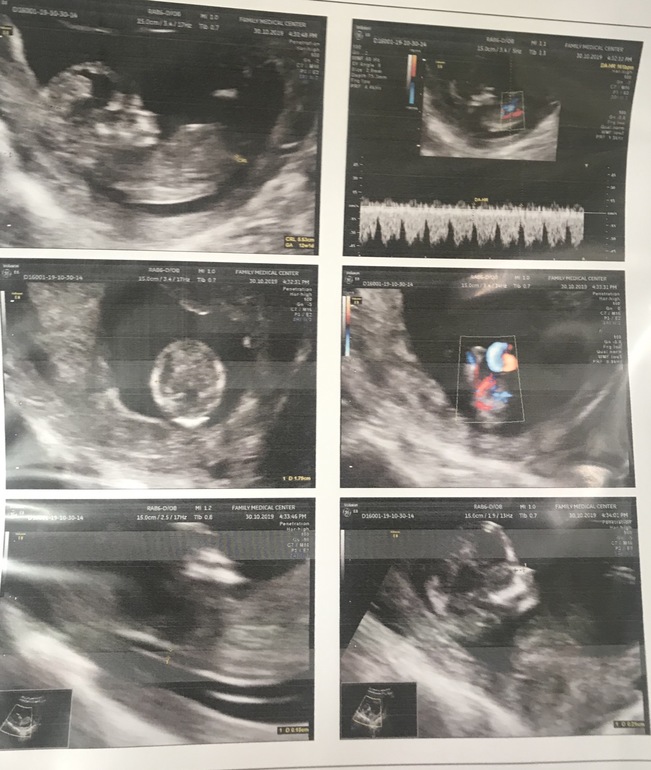

12 недель, может кто-то увидит пол ребенка?)

Привет, девочки!) Врач сказал придти через 2 недели, но может кто-то видит пол ребенка?)) знаю глупо, но хочется услышать ваше мнение😜

По половому бугорку у вас девочка, на таком сроке еще не сформированы половые органы, и пол плода определяют по половым бугоркам, почитайте в интернете и там же картинки есть. У вас половой бугорок лежит, значит девочка.

Выражение лица - суровое. Мальчик!

А если серьезно, то никак по голове не определишь 🤷♀️

Мне почему-то по строению черепа кажется что мальчик). Вот не могу объяснить почему, кажется и все тут🙂

Дождитесь второго скрининг, чтобы уж наверняка было видно, кто же там😏